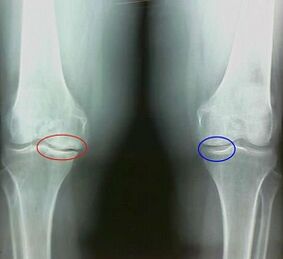

For example, what is the difference between knee arthritis and arthritis?Through arthritis, the synovial shell of joint tissue occurs.This can cause joint temperature to rise.

Joint swelling, a persistent pain syndrome development, exacerbates during exercise.With arthritis, pain only occurs after physical activity, and you can hear characteristic tightening or clicking in the joints, gradually deforming and losing mobility.

Among the symptoms of joints, there are the following distinctions:

- The pain occurs after physical activity, sudden movement, turns, tilt, and after rest, the pain passes away.

- Noting characteristic tightening in the joints.

- Pain after a prolonged rest (within 15-20 minutes of mobility) (this is related to stagnation in the joint);

- Worry about night pain caused by vein stagnation;

- The pathological inflammatory forms are accompanied by edema and pain.

- The joints are deformed and their mobility decreases.